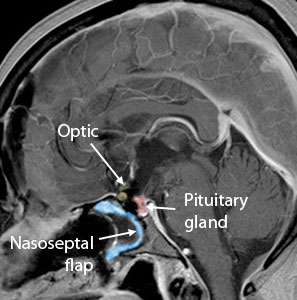

Cranio Sag After Surgery

After Surgery

Large craniopharyngioma successfully removed using the Expanded Endonasal Approach.